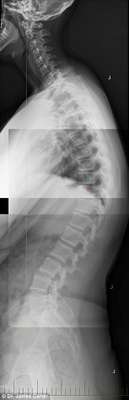

As imagens de raio-x abaixo mostram os malefícios do uso excessivo de smartphones e tablets para o corpo de adolescentes e crianças. Espinhas dorsais completamente curvadas que resultam em problemas graves de coluna e para o pescoço é a principal consequência da tecnologia para a saúde da nova geração.

17 anos, 16 anos e 7 anos

17 anos, 16 anos e 7 anos - Dr. James Carter

A condição, chamada de ‘text neck’ (‘Pescoço de mensagem’, em português), é observada em pessoas que sentam com suas cabeças a frente do corpo para interagirem com os seus smartphones ou tablets durante algumas horas.

Em geral, o peso da cabeça humana varia entre 4,5 kg e 55, kg, e a projeção do pescoço para frente faz com que o peso seja mais difícil de suportar, o que aumenta a probabilidade do surgimento de dores musculares e o encurvamento da espinha dorsal.